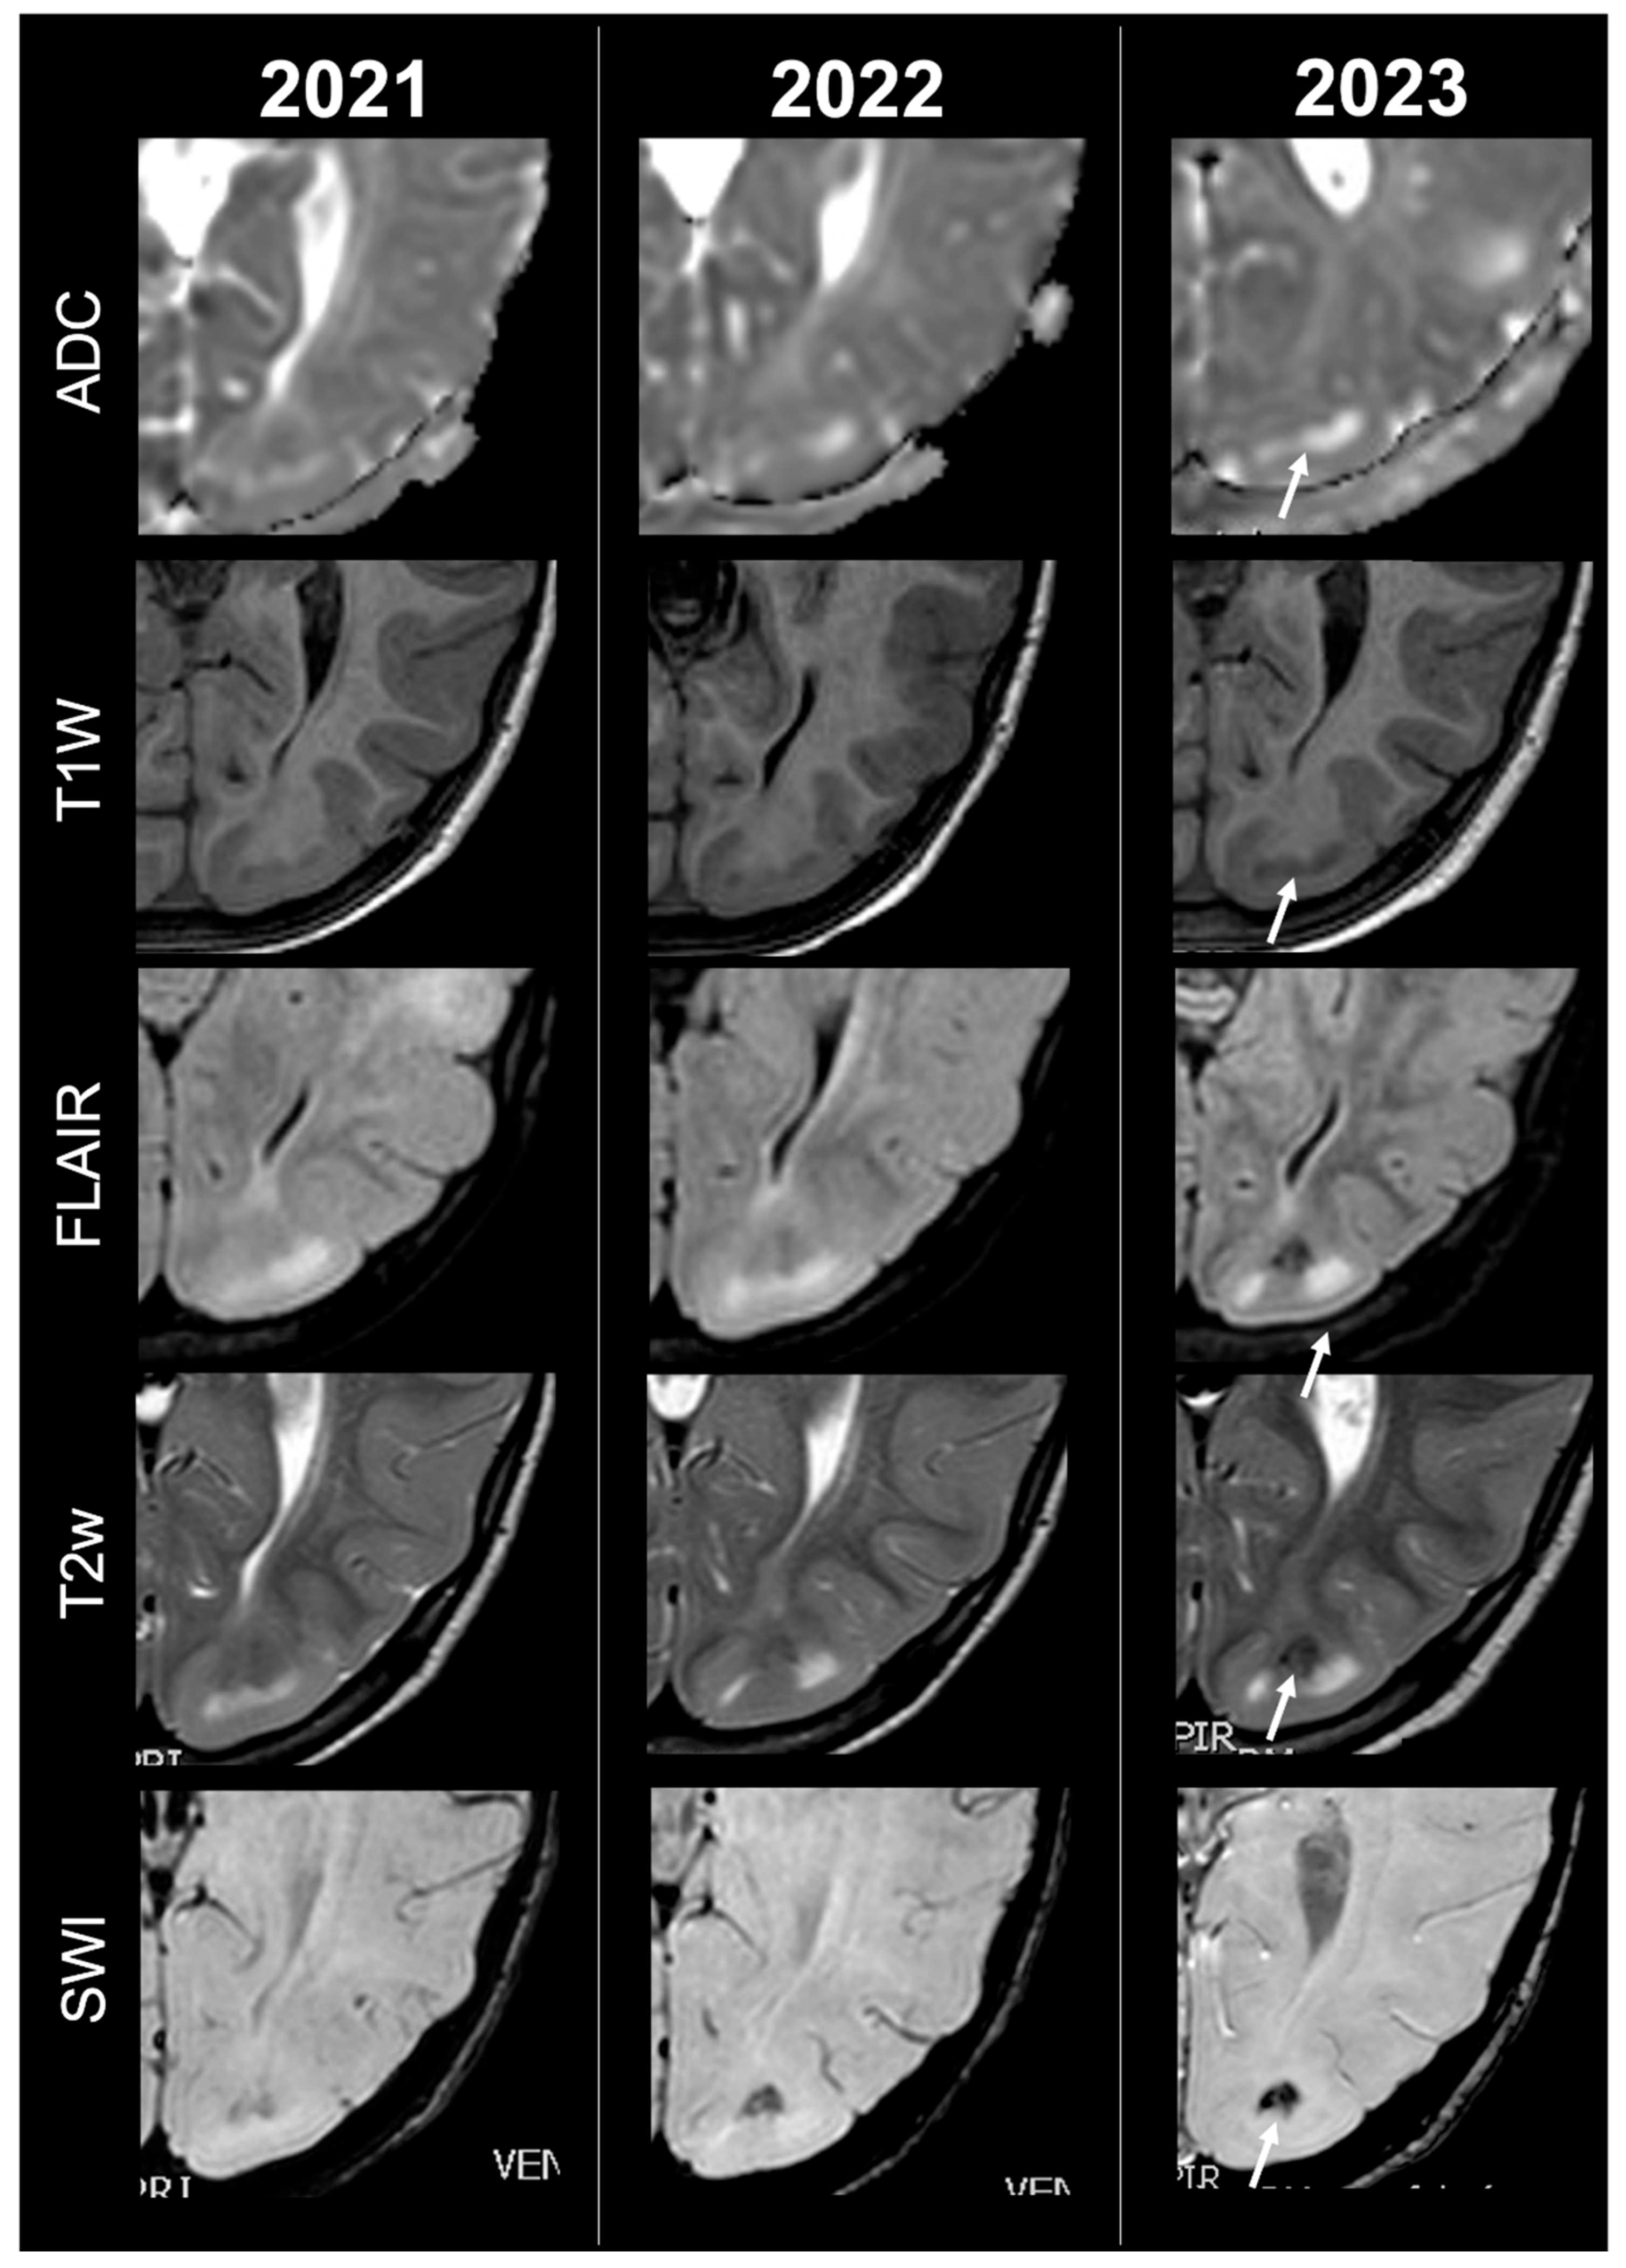

Concerning total lesion count, the interobserver agreement was excellent, with an ICC of 0.91 (95% CI: 0.87–0.95). At baseline, the total number of CTs identified across the cohort was 918 (mean ± SD = 16.1 ± 12.4), whereas at the last available MRI follow-up, the overall count increased to 1070 (mean ± SD = 18.8 ± 13.3), corresponding to a net gain of 152 CTs, equal to a relative variation of +17%. When stratified by tuber type, distinct trajectories were observed over time. Type A CTs, which were relatively abundant at diagnosis (N = 303, mean ± SD = 5.3 ± 7.0), decreased to 255 (mean ± SD = 4.5 ± 5.9) at follow-up, yielding a reduction of 48 lesions (−16%). Conversely, type B CTs showed an opposite trend, increasing from 438 (mean ± SD = 7.7 ± 8.4) at baseline to 556 (mean ± SD = 9.8 ± 8.6) at follow-up, corresponding to a net increase of 118 tubers (+27%). An example of MRI signal evolution from tuber A to tuber B is shown in Figure 1. Similarly, type C1 CTs rose from 160 (mean ± SD = 2.8 ± 4.8) to 220 (mean ± SD = 3.9 ± 5.8), with a net gain of 60 tubers (+38%). Type C2 CTs, initially rare at diagnosis (N = 14, mean ± SD = 0.2 ± 0.8), markedly expanded to 33 (mean ± SD = 0.6 ± 1.5), accounting for an increase of 19 CTs (+136%). Finally, type D CTs were only sporadically encountered, with a modest increase from 3 (mean ± SD = 0.1 ± 0.3) to 6 (mean ± SD = 0.1 ± 0.4), equating to a 100% variation. The observed increment of type C2 tubers was attributable almost exclusively to the progressive transformation of pre-existing type B lesions and, more prominently, type C1 lesions, while the increase in type C1 tubers reflected the gradual conversion of both type A and type B CTs that were already detectable at disease onset. An example of MRI signal evolution from tuber B to C1 is shown in Figure 2, while from tuber C1 to C2 in Figure 3. Only in one patient was a type C1 tuber newly identified at follow-up without clear evidence at baseline. In contrast, newly apparent tubers emerging over time but not clearly visible on baseline scans were most frequently represented by type A and type B lesions. Type D tubers were rare overall and were identified in only six lesions from four patients with a particularly high lesion burden; in all but one case they represented the evolution of type A or type B CTs (an example of MRI signal evolution from tuber A to tuber D is shown in Figure 4), while in a single case they were associated with adjacent subtle calcific foci. Overall descriptive data are summarized in Table 1.

Figure 1.

Left occipital tuber transition from type A to B at three different timepoints in a male patient diagnosed with TSC1.